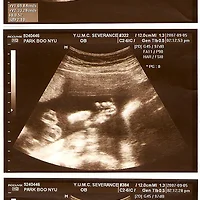

[임신22주차 배초음파 전신사진]

임신22주차에 들어서면 태아는 손톱과 눈꺼풀이 완전히 발육됩니다.

귀도 완전히 제자리를 잡습니다.

골격이 완전히 잡혀 X레이를 찍어보면 두개골, 척추, 갈비뼈, 팔다리뼈 모두 뚜렷이 구분할 수 있습니다.

태아의 길이도 18-19cm이고 몸무게는 300-750g 정도입니다.

아가의 키는 19cm이고 몸무게는 400g 으로 자랐어요.